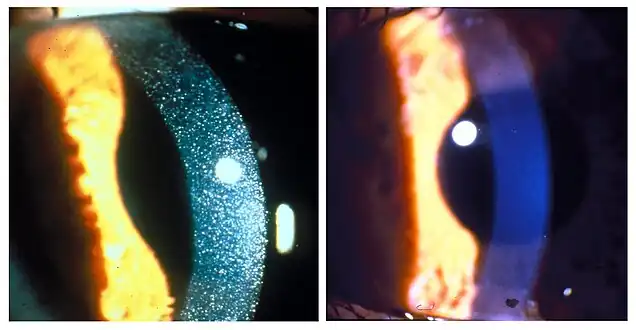

Rickets in cystinosis. a- A cystinosis child with evident rachitic bone deformities. b- Active rachitic bone disease in X-Rays Slit-lamp photographs of three-year-old patient with nephropathic cystinosis before (left) and after (right) cysteamine eyedrop therapy. The drops dissolve the crystals in the cornea.

Slit-lamp photographs of three-year-old patient with nephropathic cystinosis before (left) and after (right) cysteamine eyedrop therapy. The drops dissolve the crystals in the cornea.